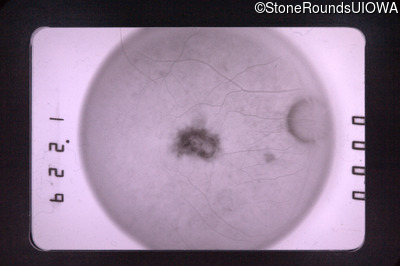

Fluorescein Angiography - Right - 20/30

Exemplar